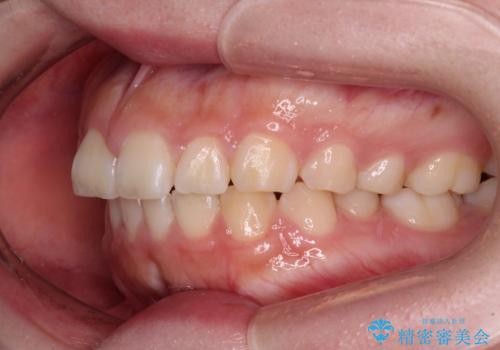

抜歯矯正を行ったことで、顎先のつっぱり感や口元の閉じにくさを解消することができました。